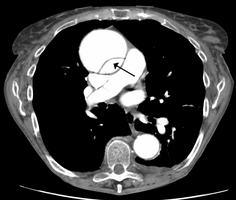

Type A dissection with pericardial effusion as a result.